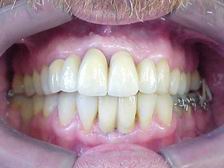

Aspecto final após glazeamento da cerâmica e remoção do aparelho ortodôntico

Metalocerâmica sobre implantes (CONCLUÍDO)